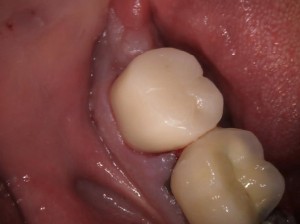

The process of a root canal starts with cleaning the hollow space that is created inside the infected tooth and then is filled to stop further infection. In most cases, the next step is to put on a porcelain crown to give it extra strength. The entire process is done under the local anesthetic at the Amity Dental Centre in the safe hands of Dr. Nohra which guarantees no discomfort or pain.